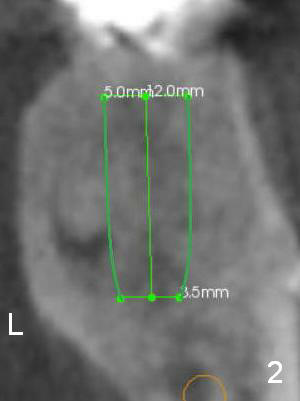

A 40-year-old man will return to clinic for #19 implant placement, probably due to crown fracture (Fig.1 (CT sagittal section) >: open margin of PFM crown). In fact implants have been placed at #20 and 21. After extraction of #19 and socket debridement without antibiotic, a 5x12 mm implant is to be placed in the tripod septum (Fig.2 (coronal section; L: lingual),3 ((axial section) M: mesial; DB: distobuccal; DL: distolingual (root)). An abutment with the largest diameter (7.8 mm) will be chosen to close the socket as much as possible (Fig.1 pink). Bone density is high (600-900 U). Drills will be used for osteotomy. The initial depth is 12 mm with stop on the septal crest. Take photos preop to show residual roots.